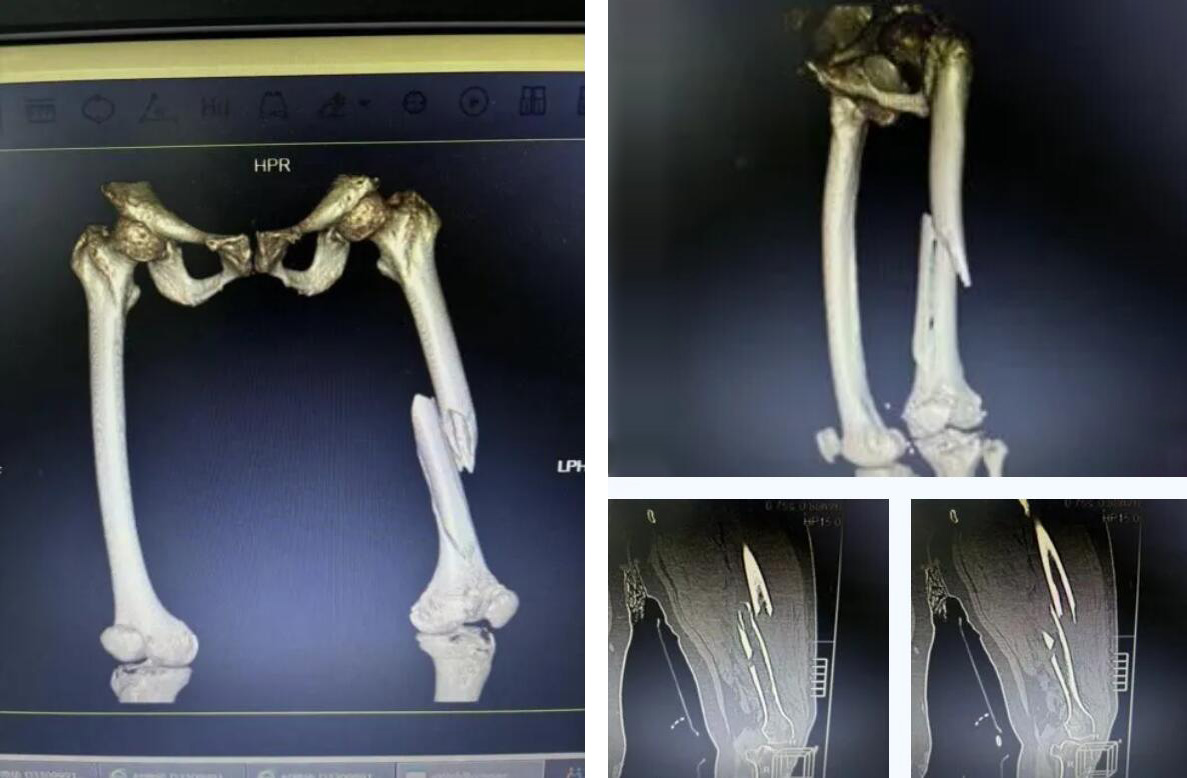

經(jīng)檢查確診為 “右股骨多段粉碎性骨折”??紤]到俞奶奶年事已高,身體機(jī)能衰退,當(dāng)?shù)蒯t(yī)院認(rèn)為手術(shù)風(fēng)險(xiǎn)極大,建議轉(zhuǎn)院治療。

術(shù)前患者骨折CT影像

而俞奶奶的股骨中段的多段骨折,手術(shù)難度和風(fēng)險(xiǎn)更是呈幾何級數(shù)增加,傳統(tǒng)的開放手術(shù)創(chuàng)傷大、出血多,老人脆弱的心肺功能難以承受。